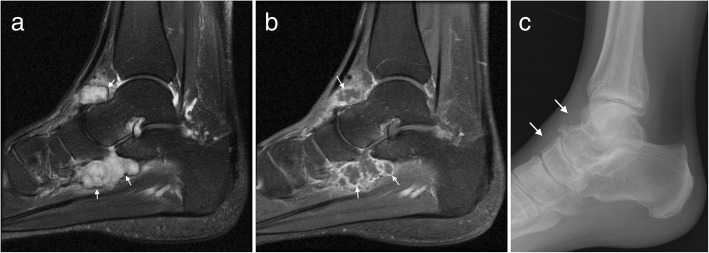

Fig. 9.

Synovial chondromatosis. a Sagittal T2FS image of the ankle demonstrating a lobulated T2 hyperintense lesion with a low signal rim (arrows) and b avid synovial enhancement on post contrast T1FS imaging (arrows). c Mineralisation is better appreciated on the corresponding radiograph (arrows).

In the late stage, plain radiographs or CT may demonstrate numerous intra-articular mineralised bodies with secondary osteoarthritis. Earlier in the disease, non-mineralised intra-articular bodies present a more challenging diagnosis. In the initial proliferative phase, a lobulated intra-articular lesion is typical, with intermediate to slightly hyperintense signal on T1W and high signal on T2W (Fig. 9) [14, 16, 19]. Later, mineralised nodules may be seen as signal voids on all sequences, or as ossified bodies with a low signal cortex and central fatty marrow signal [14, 16, 19]. Correlation with radiographic appearances can be helpful to further delineate and classify any foci of mineralisation. Post contrast imaging shows enhancement of the hyperplastic synovium, more pronounced in the earlier stage [14, 16].